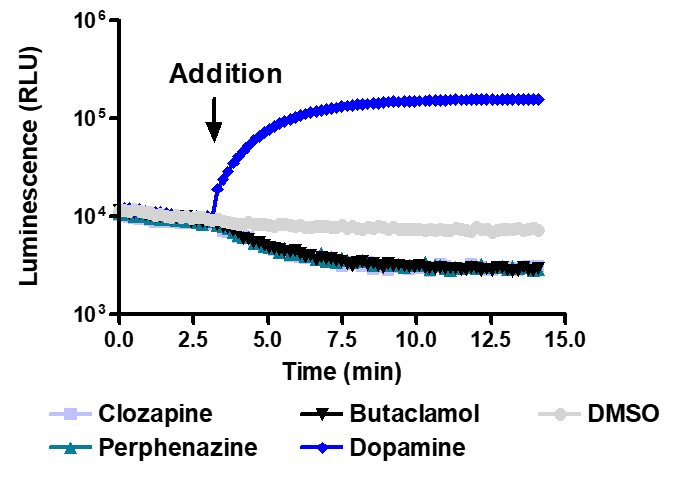

Sensitive enough to detect inverse agonists without forskolin. HEK293 cells expressing Dopamine D1 receptor were transiently transfected with pGloSensor™-22F cAMP Plasmid and treated with 10µM compounds at 28°C.